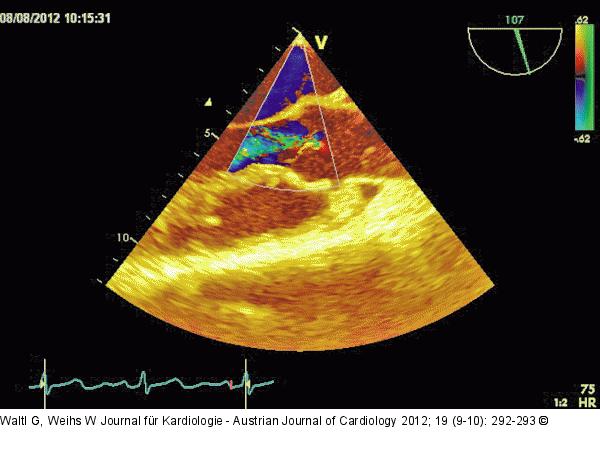

Abbildung 6: Transösophageales Echo Transösophageale Echokardiographie mit Darstellung der Aortenklappe im Querschnitt mit Farbdoppler: Zentrale (schmale) Regurgitation an der Koaptationsstelle der 4 Klappentaschen. |

Transösophageale Echokardiographie mit Darstellung der Aortenklappe im Querschnitt mit Farbdoppler: Zentrale (schmale) Regurgitation an der Koaptationsstelle der 4 Klappentaschen. |